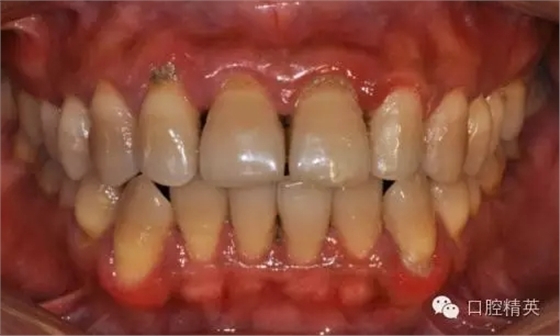

本病例 :女 34歲,主訴刷牙出血,覺(jué)牙齒輕度松動(dòng)一年。

檢查見(jiàn)大量齦上及齦下結(jié)石,探診出血,牙周袋較深,32-42 II度松動(dòng)。X線片顯示牙槽骨水平吸收。

診斷:成人慢性廣泛性中度牙周炎。

治療計(jì)劃:口腔衛(wèi)生宣教,刷牙指導(dǎo),齦上潔治,齦下刮治術(shù),下頜牙33-43牙周固定。

治療前: